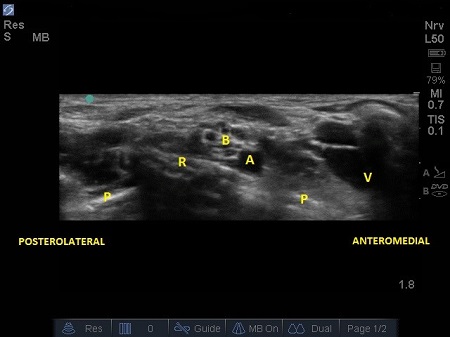

- The probe should be angled/tilted till an optimal image is obtained where we can clearly identify these four structures: the subclavian artery, the first rib, the pleura and the brachial plexus.

- The first structure to locate is the round pulsating hypoechoic subclavian artery (A), lying on top of the hyperechoic first rib (R). Use Doppler to assess for vessels. See Fig. 2.

- The subclavian vein (V) is found more medially to the artery. The anterior scalene muscle inserts onto the first rib between these two vessels (A and V), but occasionally there are anatomical variations (4) where both vessels are together between the insertions of both the scalene muscles (anterior and middle ones).

Fig. 3. Sonoanatomy of infant supraclavicular region. A – Subclavian artery. B – brachial plexus, P – pleura, R – first rib, V – subclavian vein

- Lateral and above the artery sit a bundle of round hypoechoic circles (“bunch of grapes” or “cluster of bubbles”) – the brachial plexus, at this level, the plexus will be configured as trunks and/or divisions.

- It may be possible to identify the hypoechoic nodules surrounded by a hyper-reflective fascial sheath.